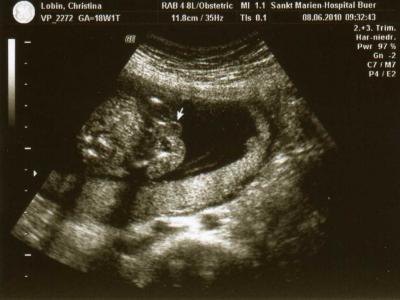

sooo da bin ich wieder. erstmal danke mausi, das du hier sofort bescheid gegeben hast! und auch danke für deine lieben sms! ganz dicken: jetzt erkläre ich euch nochmal warum ich überhaupt ins kh musste, maus hat das schon ganz gut gemacht. meine tochter saß auf meinem schoß und ist ruckartig schnell nach hinten gerutscht, dabei ist sie mir heftig gegen den bauch gestoßen. ich hatte mir nichts dabei gedacht, doch später als ich auf der toilette war habe ich gesehen, dass einiges an flüssigkeit ausgelaufen ist. beim gehen ziepte es auch ein wenig im bauch, wir sind daraufhin sofort ins kh und alles wurde kontrolliert. es war gott sei dank kein fruchtwasser und dem kleinen geht es super, die flüssigkeit kam von dem aufprall aus der harnblase...ja man könnte also sagen, dass ich mir unbewusst in die hose gepieselt habe. ist aber völlig normal bei einem "stumpfen bauchtrauma" jetzt hat das ganze auch mal einen namen... zur beobachtung musste ich aber trotzdem 2 tage im kh bleiben, es wurde jeden tag ein us gemacht, auch um nach der plazenta zu schauen (plazenta-ablösung) heute morgen durfte ich dann nach hause, es ist alles in ordnung! dafür habe ich jetzt aber das nächste problem, ich plage mich ja schon seit wochen mit rückenschmerzen rum und jetzt geht gar nichts mehr, der ischias nerv ist eingeklemmt und es tut sau weh, beim laufen kann ich kaum mit dem linken bein auftreten und wirklich jede haltung, egal ob ich auf der linken seite liege, auf der rechten oder auf dem rücken schmerzt. am besten ich sitze auf einem knallharten stuhl, ganz gerade, dann geht es einigermaßen. aus der ss meiner tochter kenne ich sowas gar nicht, da wurde ich wohl ziemlich verwöhnt. naja, da muss ich jetzt wohl durch, wenn es noch schlimmer wird, werde ich aber medis nehmen müssen. so und hier noch ein eindeutiges outing bild, es wird zu 99% ein junge! auf dem foto sieht man die hoden.

Bild zu Zurück aus dem Krankenhaus - Forum für November - Mamis